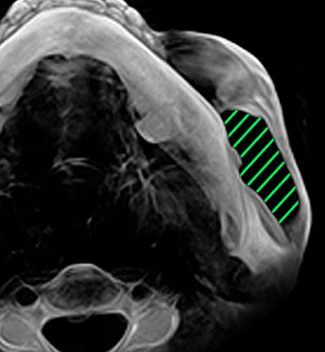

과도하게 발달된 사각턱을

절제하고 귀밑 각을

자연스럽게 살려

남자다운 턱라인 완성

실제 수술환자 CT 전후사진

과도하게 발달된 사각턱을 절제하고

귀밑 각을 자연스럽게 살려